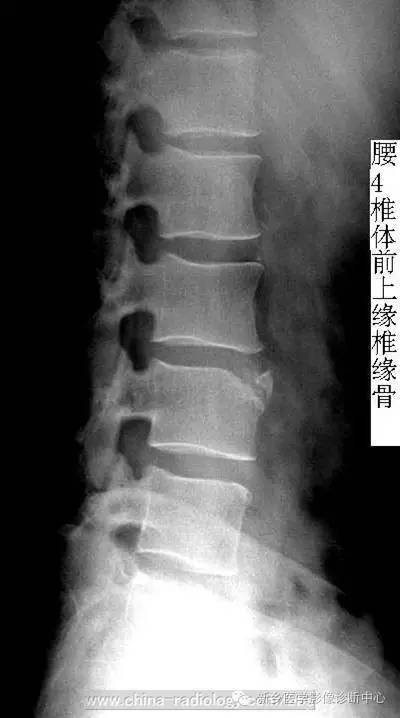

X线表现正位相常无异常发现,侧位片显示椎体后上或后下角有弧状或切迹状骨质缺损区,边缘硬化或毛糙不整,后缘为斜面与缺损区相对应。游离骨块与椎体之间夹有一条厚薄不一的透光带,骨块可全部或部分与椎体分离突入椎管。。